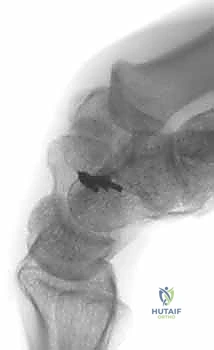

Image

FIG 2 • B. CT scan of a patient with pain over the dorsal aspect of his left radiocarpal joint, showing a non-widened space between scaphoid and lunate, useful for baseline comparison.